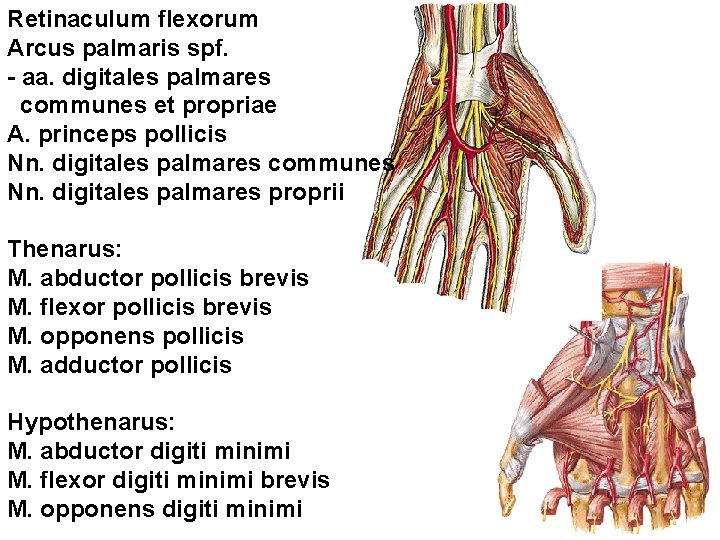

Retinaculum flexorum Arcus palmaris spf. - aa. digitales palmares communes et propriae A. princeps pollicis Nn. digitales palmares communes Nn. digitales palmares proprii Thenarus: M. abductor pollicis brevis M. flexor pollicis brevis M. opponens pollicis M. adductor pollicis Hypothenarus: M. abductor digiti minimi M. flexor digiti minimi brevis M. opponens digiti minimi

Rete carpi palmare Arcus palmaris prof. - aa. metacarpeae palmares R. prof. n. ulnaris

Mm. lumbricales Mm. interossei palmares Mm. interossei dorsales